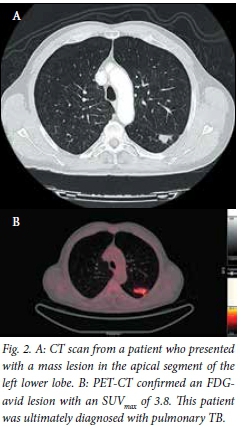

Chest radiograph and CT findings

The average diameters of the lesions measured were 29 mm in the vertical axis and 30 mm in the horizontal axis on standard anteroposterior (AP) chest radiograph, and these were very similar to the CT measurements (Figs 1 and 2). Lesions ultimately proven to be malignant were most frequently observed in the right (n=12) and left upper lobes (n=8).

PET-CT findings and SUVmax